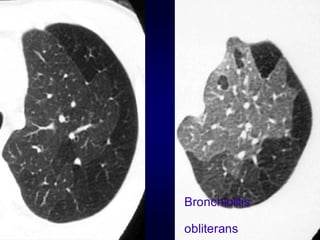

Bronchiolitis obliterans (constrictive bronchiolitis)

idiopathic, connective tissue diseases, drug reaction,

after transplantation, after infection

Bronchiolitis

obliterans

Airway Disease what yousee…… In inspiration sharply demarcated areas of seemingly increased density (normal) and decreased density demarcation by interlobular septa In expiration ‘black’ areas remain in volume and density ‘white’ areas decrease in volume and increase in density INCREASE IN CONTRAST DIFFERENCES AIRTRAPPING